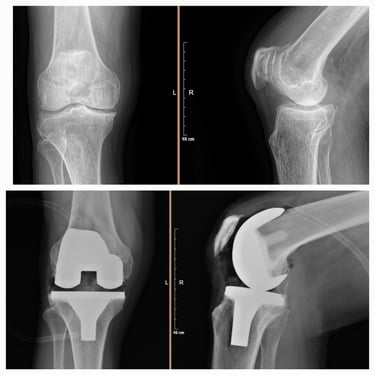

Artroplastia de rodilla (prótesis total/parcial).

Cirugía de revisión de cadera y rodilla.

Desgaste articular de cadera y rodilla.

Manejo de secuelas y complicaciones de prótesis de cadera y rodilla.